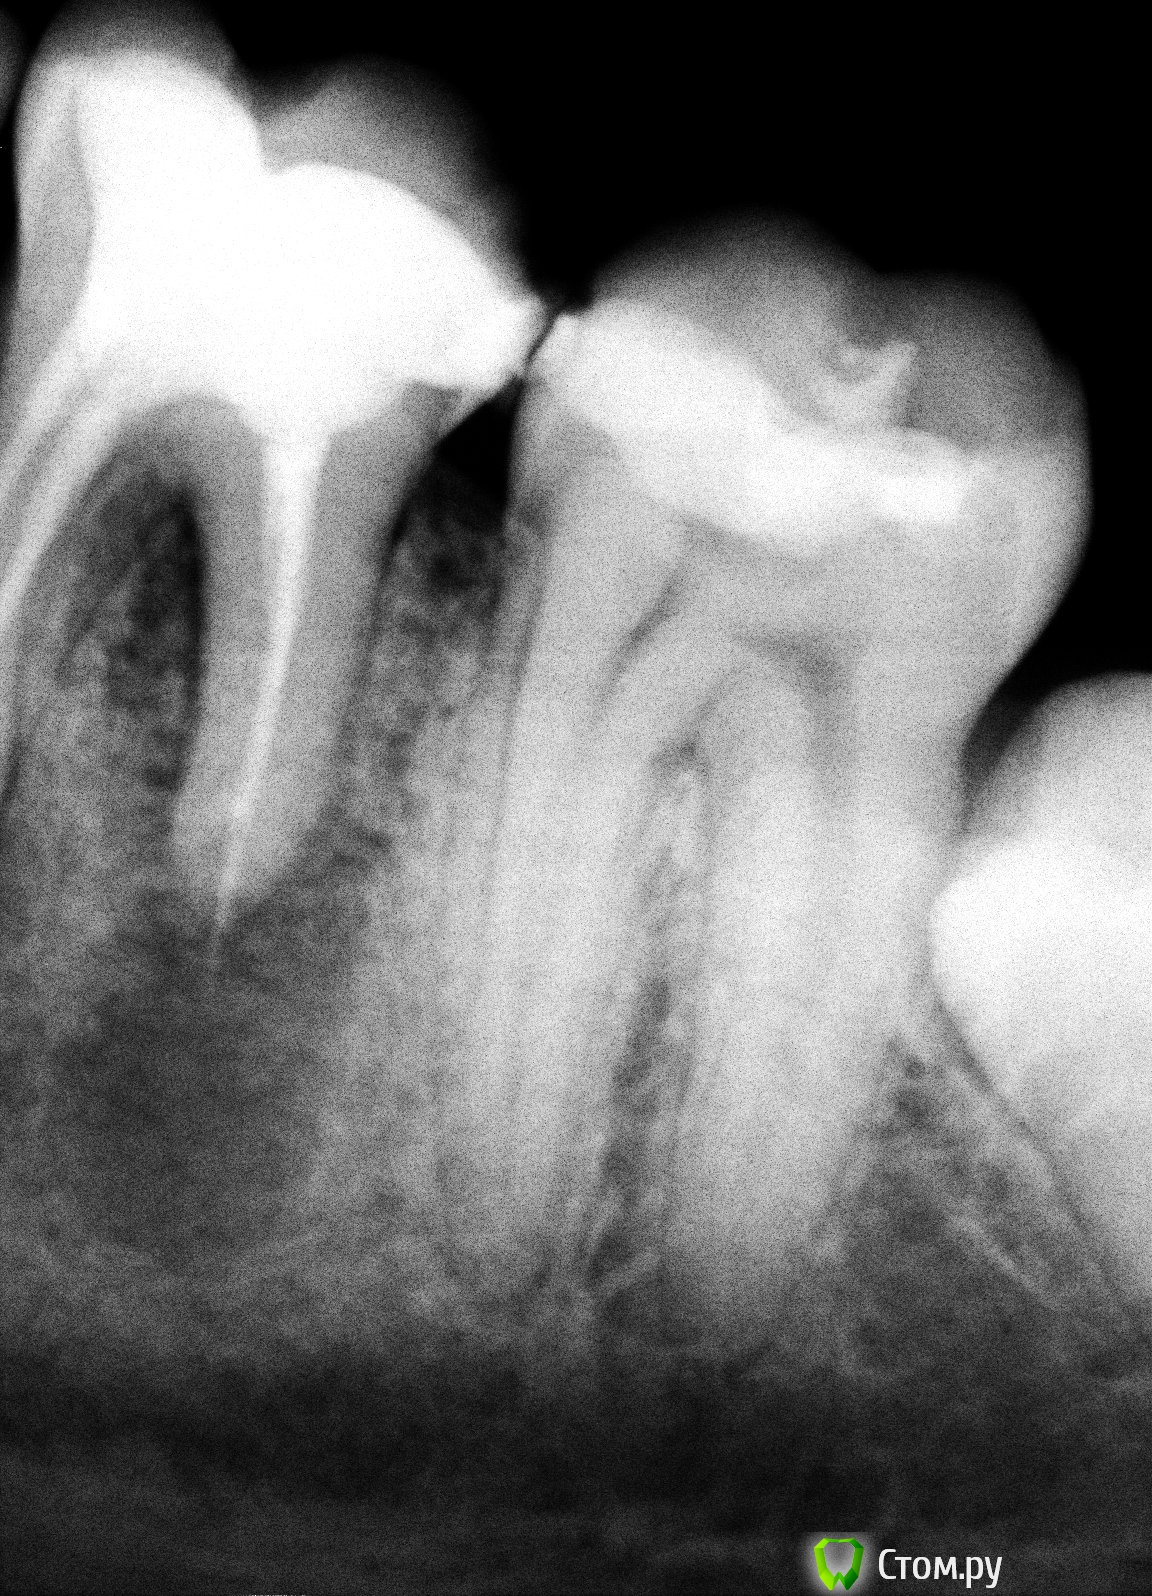

vovka2 Опубликовано 16 января, 2014 Поделиться Опубликовано 16 января, 2014 (изменено) Добрый день хотел задать вопрос по поводу кисты зуба. Около 5 лет назад разболелся 6 нижний левый зуб пошел к стоматологу зуб поставлена была временная пломба, затем на второй приход зуб депульпировали и поставили пломбу. Недавно этот зуб немножко надломился с краешку незначительно. Перед тем как исправить дефект на зубе врач на всякий случай сделали рентген и сказал что там киста и надо удалять зуб, что лечение в данном случае не принесет результатов.Хотелось бы узнать ваше мнение доктора насколько срочная ситуация. Тк зуб абсолютно не беспокоит. Заранее благодарю.. Снимки прилагаются.. Изменено 16 января, 2014 пользователем vovka2 Ссылка на комментарий

DmitrySH Опубликовано 16 января, 2014 Поделиться Опубликовано 16 января, 2014 Я предложил попробовать лечение. Ничего очень страшного тут не вижу. Ссылка на комментарий

DmitrySH Опубликовано 17 января, 2014 Поделиться Опубликовано 17 января, 2014 опять мнения разделились )) Так это же хорошо. По теме считаю, что вопрос можно решить и хирургически и терапевтически. 1 Ссылка на комментарий